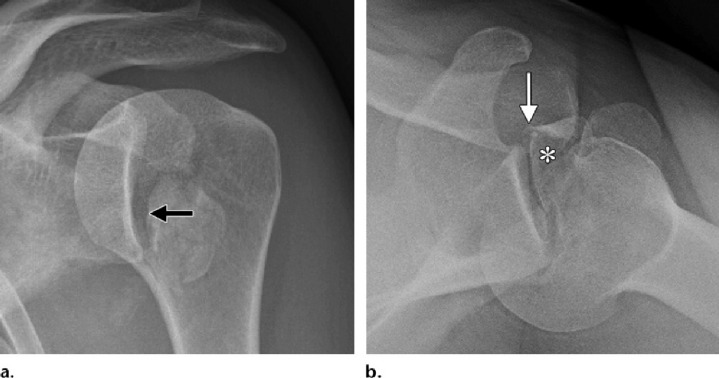

It is standard procedure to take simple anteroposterior radiographs both before and after a dislocation. Anteroposterior radiographs are the only imaging tests often performed during an emergency. Doctor usually perform axillary and/or transcapular projection if they suspect a posterior dislocation, even they don’t know which way the force is coming from. There is a 50% chance that anteroposterior radiography will overlook posterior dislocations. In the absence of other perspectives, a multitude of frontal indicators may be used to identify posterior dislocation. At the location of the impact fracture on the anterior humeral head, a sclerotic line may be seen in the axillary view. Reason being, a 6 mm or greater rise in the articular distance indicates either the trough indication or the rim sign.14

When the direction of the force cannot be determined, CT imaging is the suggested method. Dislocation in conjunction with a bony-Bankart lesion and a larger tuberosity fracture are also covered in depth. CT scans, using the best-fit circle method in the sagittal plane, provide the most precise evaluation of glenoid injury. It is crucial to diagnose glenoid bone loss because instability is likely to occur when a defect affects more than 20% of the entire glenoid surface or more than 7 mm in width.15